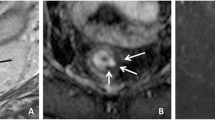

Two readers with experience reading rectal MRI (Reader 1: AMH with 5 years of experience; Reader 2: MJG with 10 years of experience) independently assessed each pre- and post-treatment MRI, blinded to clinical and histopathological information. They each assessed the following metrics, which were chosen either because they were already frequently used for tumour assessment or because they had been reported to provide significant value in response assessment on rectal MRI after therapy (see Fig. 2 a–d for examples):

(a) T2- weighted image (sagittal): Measurement of longest tumour diameter. (b) T2- weighted image (axial-oblique): Measurement of product of largest bidirectional measurements (excluding the lumen) and T2 volumetry (region of interest (ROI) was drawn on every slice with visible tumour). (c) diffusion-weighted image (axial, b=1000 s/mm2): tumour volumetry on diffusion-weighted imaging (DWI; ROI was drawn on every slice with visible tumour) and calculation of apparent diffusion coefficient (ADC). (d) T1- weighted dynamic contrast-enhanced (DCE) image (sagittal): tumour volumetry on DCE. Ktrans was derived from a ROI in maximal tumour extent